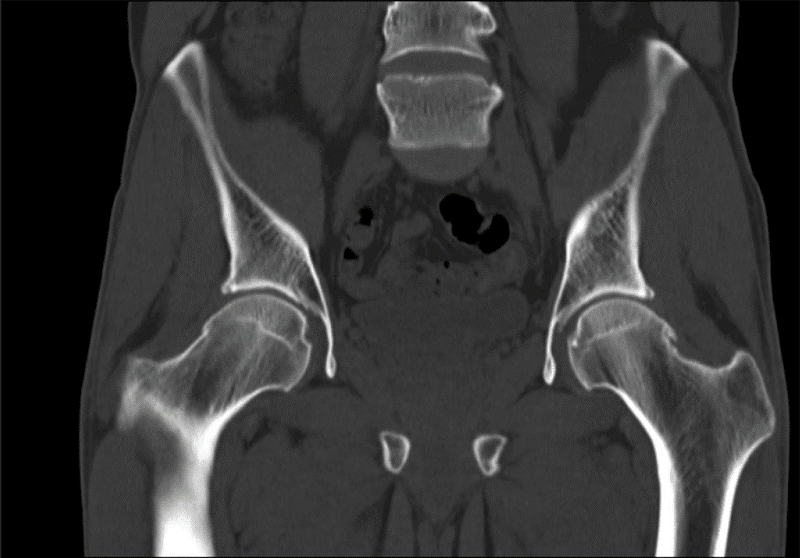

Bilgisayarlı Tomografi (BT)

Bilgisayarlı tomografi (BT), röntgen ve bilgisayar sistemlerinden oluşur. Vücudumuzun çeşitli bölgelerinin görüntülerini kesitler halinde verir. Çekim ağrısızdır. Bir röntgen tüpü hastanın etrafında döner ve farklı açılardan görüntüler oluşturur. Bir bilgisayar aracılığı ile bu görüntüler ekrana yansıtılır ve film haline getiriler. Daha net görüntüler elde etmek için, hastaya radyopak maddeler içirilebilir veya enjekte edilebilir.

Bilgisayarlı tomografi vücudun çeşitli bölgelerinin görüntülerini kesitler halinde verir.

• Yer değiştirmiş kemik fragmanlarının tanınması

• Kemik defektlerinin tespiti

• Omuz çıkıklarının ayrıntılı tanımı

• Karmaşık anatomik yapıların değerlendirilmesi

• Ekstremite travmalarında eşlik eden damar yaralanmalarının tespiti

• Kemik tümörlerinde patolojik kırık olasılığının belirlenmesi

• Kas iskelet sistemi lezyonlarının biyopsi ya da aspirasyonu

• Kemik mineral yoğunluğu ölçümü yapılabilmektedir.